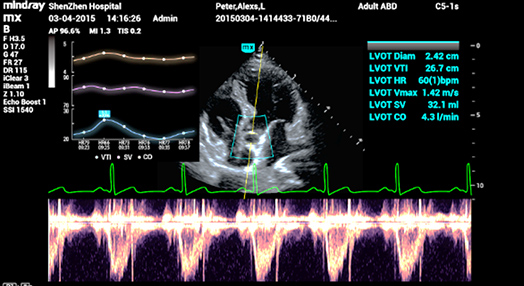

2Smart VTI (ITV)

Mesure automatique de lâintÃĐgrale temps Vitesse (ITV) et du dÃĐbit cardiaque pour permettre une ÃĐvaluation rapide de la fonction cardiaque. Lâoutil place automatiquement la boite couleur et la ligne de tir du doppler pulsÃĐ en temps rÃĐel. Un graphique de tendances reprÃĐsentant le dÃĐbit cardiaque, le volume dâÃĐjection systolique et lâITV aide à la prise de dÃĐcision.